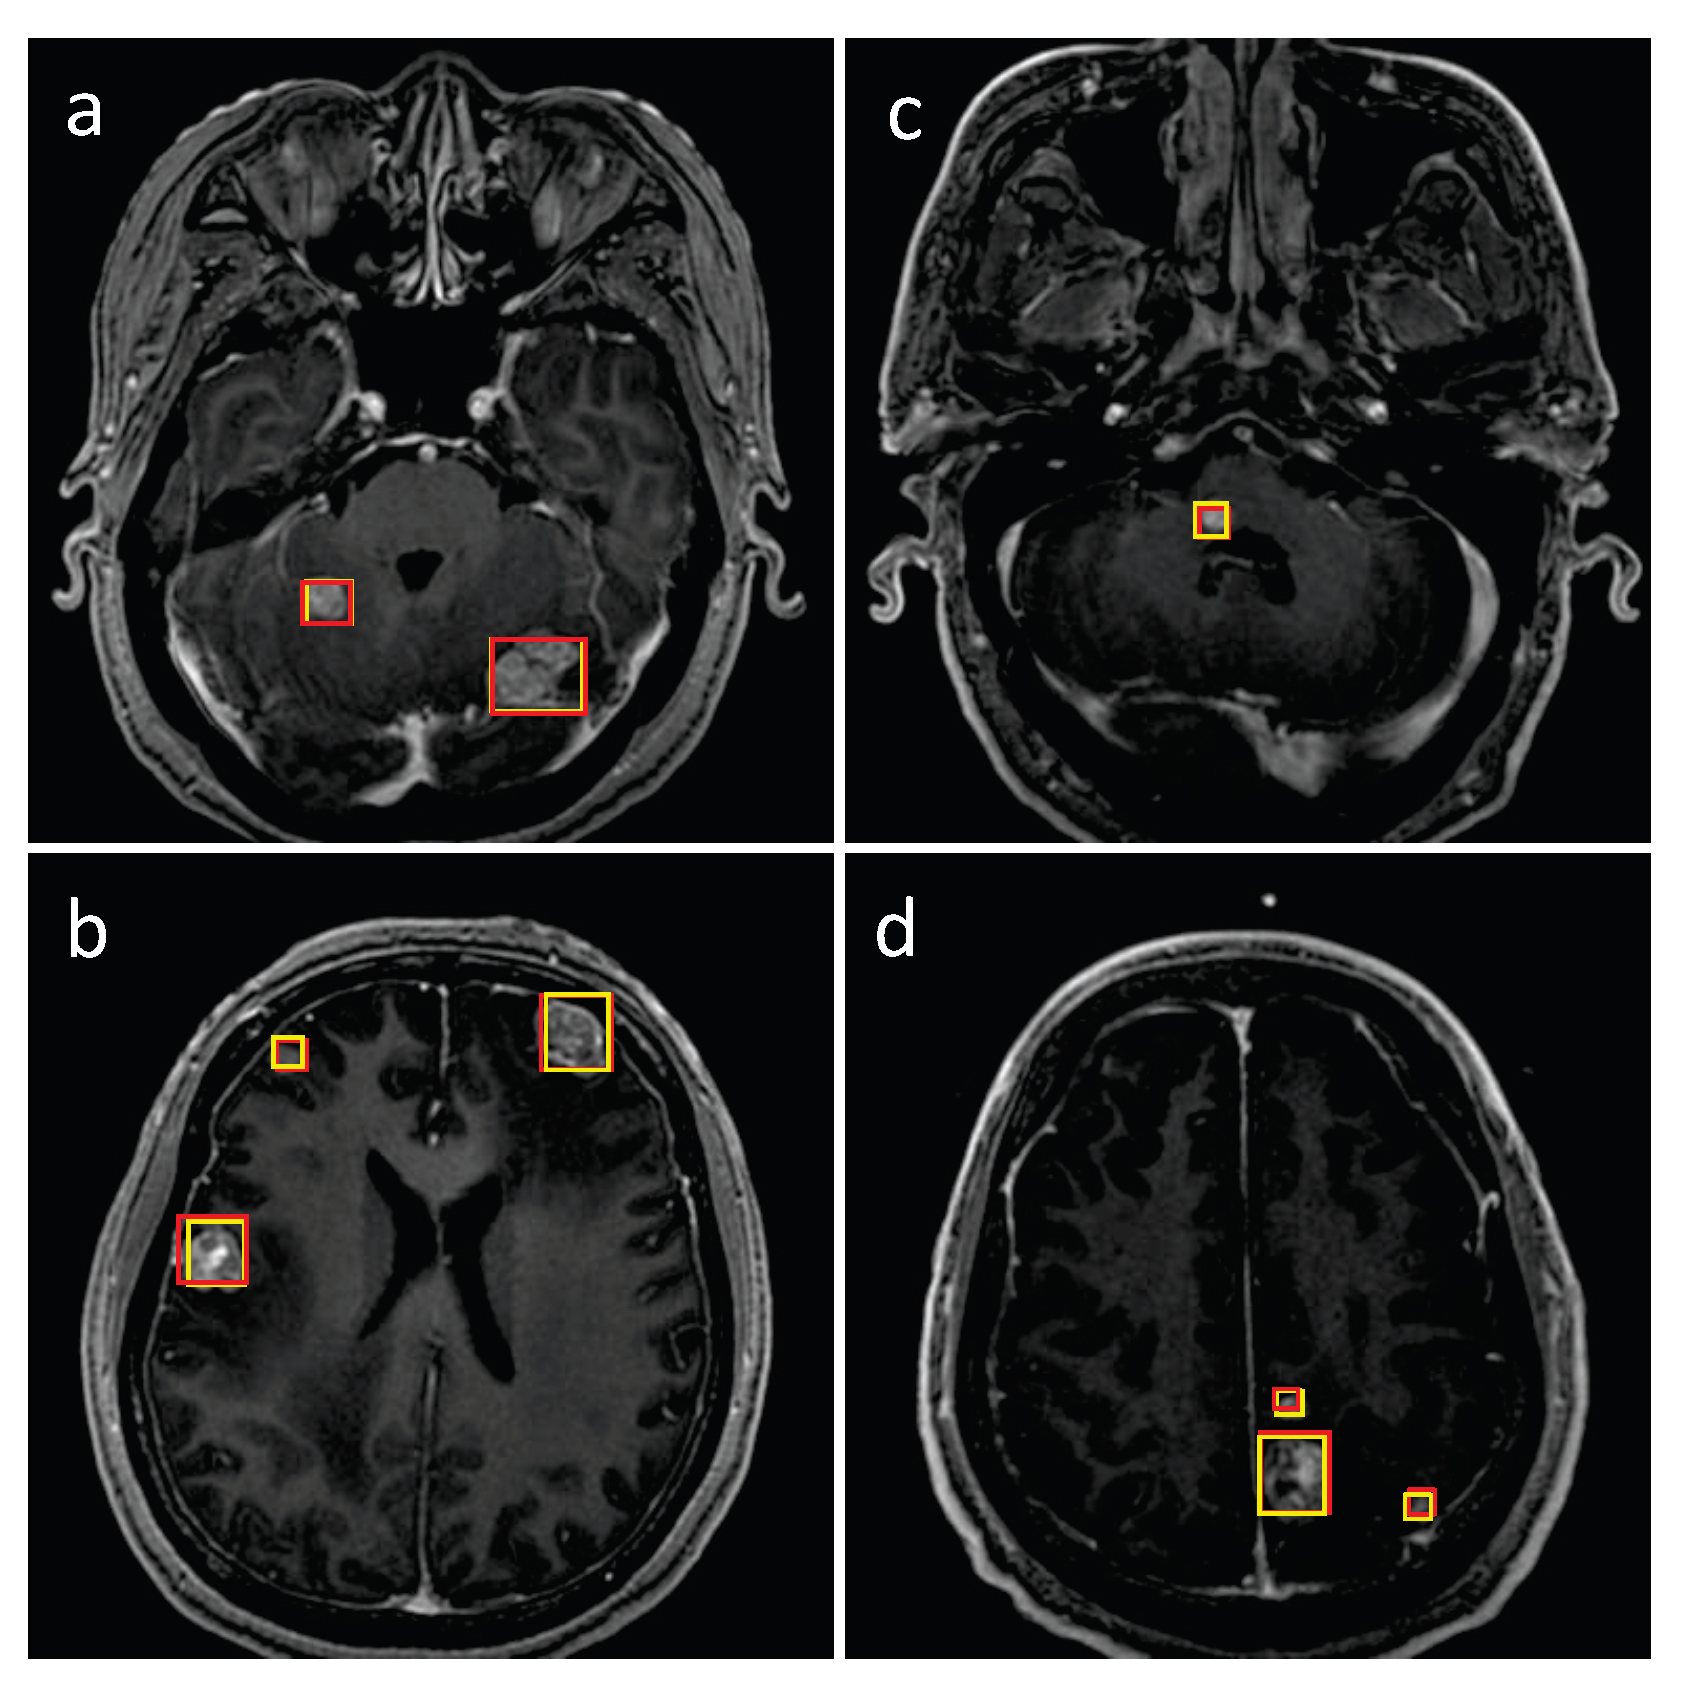

3.1. Detection Performance of SA-YOLOv5

3.4. Detection Performance on the External Testing Set